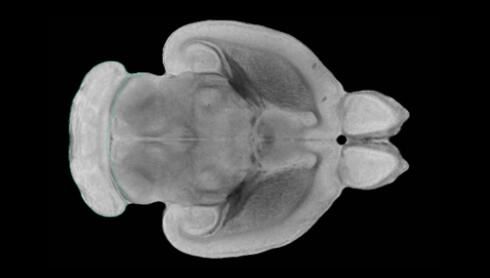

隨著機體年齡增加,肌肉和關(guān)節(jié)都會變得僵硬,這就會使得日?;顒幼兊酶永щy,本文研究表明,我們的大腦也是如此,與年齡相關(guān)的大腦僵硬對大腦干細胞的功能或許有著重要影響。文章中,研究人員對年輕和老化大鼠的大腦進行研究闡明了年齡相關(guān)大腦僵硬對少突膠質(zhì)前體細胞(OPCs,oligodendrocyte progenitor cells)功能的影響。OPCs是一類對維持正常大腦功能非常重要的大腦干細胞,其對于髓磷脂的再生也非常重要,髓磷脂是神經(jīng)組織周圍的脂肪鞘,在多發(fā)性硬化癥中髓磷脂的再生常常會被損傷,機體老化對這些細胞的影響常常會誘發(fā)多發(fā)性硬化癥的發(fā)生,這些細胞的功能在老化的健康人群中同樣會下降。

為了確定老化OPCs的功能缺失是否可以被逆轉(zhuǎn),研究人員將來自老化大鼠機體的老化OPCs轉(zhuǎn)移到了年輕大鼠柔軟的海綿狀大腦組織中去,值得注意的是,這些老化的大腦細胞能夠重新恢復活力,其行為非常像年輕更加強壯的細胞。這項研究中,研究人員在實驗室中開發(fā)出了具有可變僵硬程度的新型材料,并在受控環(huán)境下研究這些材料的生長及其對大鼠大腦干細胞的影響,這些材料能被工程化改造具有和年齡或老化大腦相似的柔軟程度。

為了深入理解大腦組織柔軟和僵硬影響細胞行為的分子機制,研究人員對細胞表面一種名為Piezo1的蛋白質(zhì)進行了分析,該蛋白質(zhì)能“告知”細胞其周圍的環(huán)境為柔軟或僵硬。研究者Kevin Chalut說道,我們發(fā)現(xiàn),當在僵硬材料上促進年輕具有功能性的大鼠干細胞時,這些細胞就會表現(xiàn)出功能異常,并失去其再生的能力,實際上其行為與老化細胞相似。當將老化的大腦細胞在柔軟材料上生長時,其功能就會表現(xiàn)得像年輕細胞一樣,換句話說,其能夠重新恢復年輕的活力。